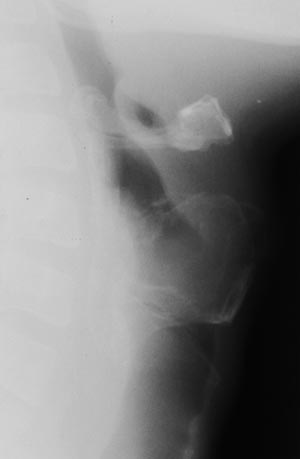

Рис. 1. Обзорная боковая рентгенограмма гортани.